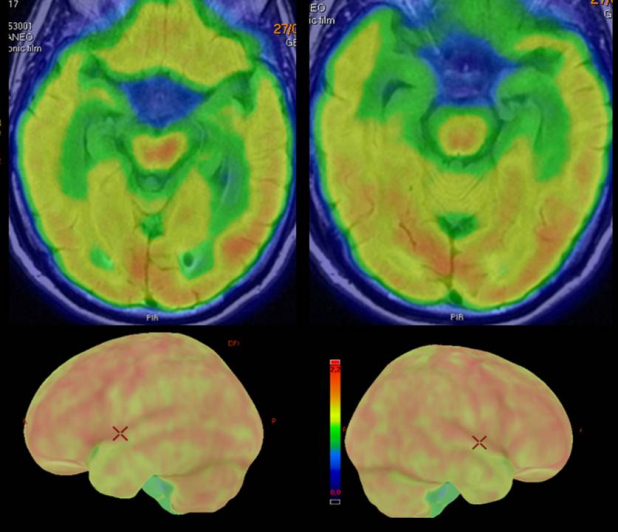

Se realizó PET-RM con 18F-FDG, que evidenció descenso de la actividad neuronal en polo anterior y neocórtex anterolateral de ambos lóbulos temporales, de forma más marcada en el lado derecho, donde se ve comprometido parcialmente el neocórtex póstero-lateral (fig. 2).